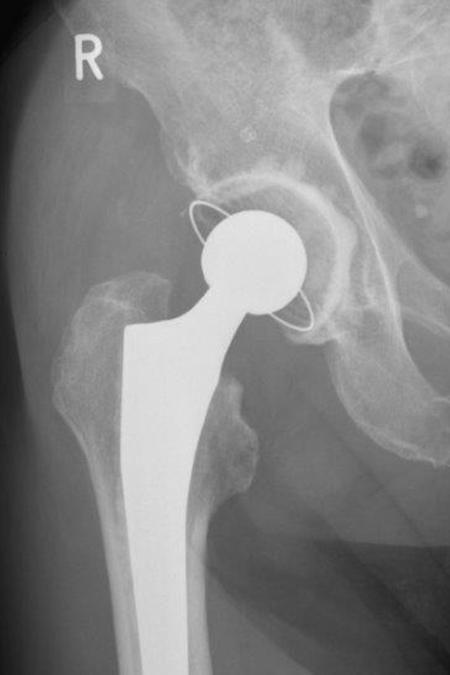

DIE FOLGENDEN BILDER ZEIGEN BEISPIELHAFT RÖNTGENERGEBNISSE NACH OPERATIVER BEHANDLUNG IN UNSERER ABTEILUNG:

Künstliches Hüftgelenk bei instabilen und verschobenen Brüchen

03/2021 – 76 jährige Frau mit wahrscheinlich durch Osteoporose bedingtem Bruch des Schenkelhalses rechts. Es wurde ein zementierter Standardschaft verwendet, der eine gleichmäßige Krafteinleitung in den Knochen des Oberschenkels gewährleistet.  Verlauf sonst unkompliziert mit guter Gelenkfunktion bereits 2 Monate nach Operation. Die Osteoporose sollte durch Bewegung und Medikamente über einen längeren Zeitraum behandelt werden.

Planung der Hüftendoprothese